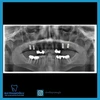

Implant tedavisi